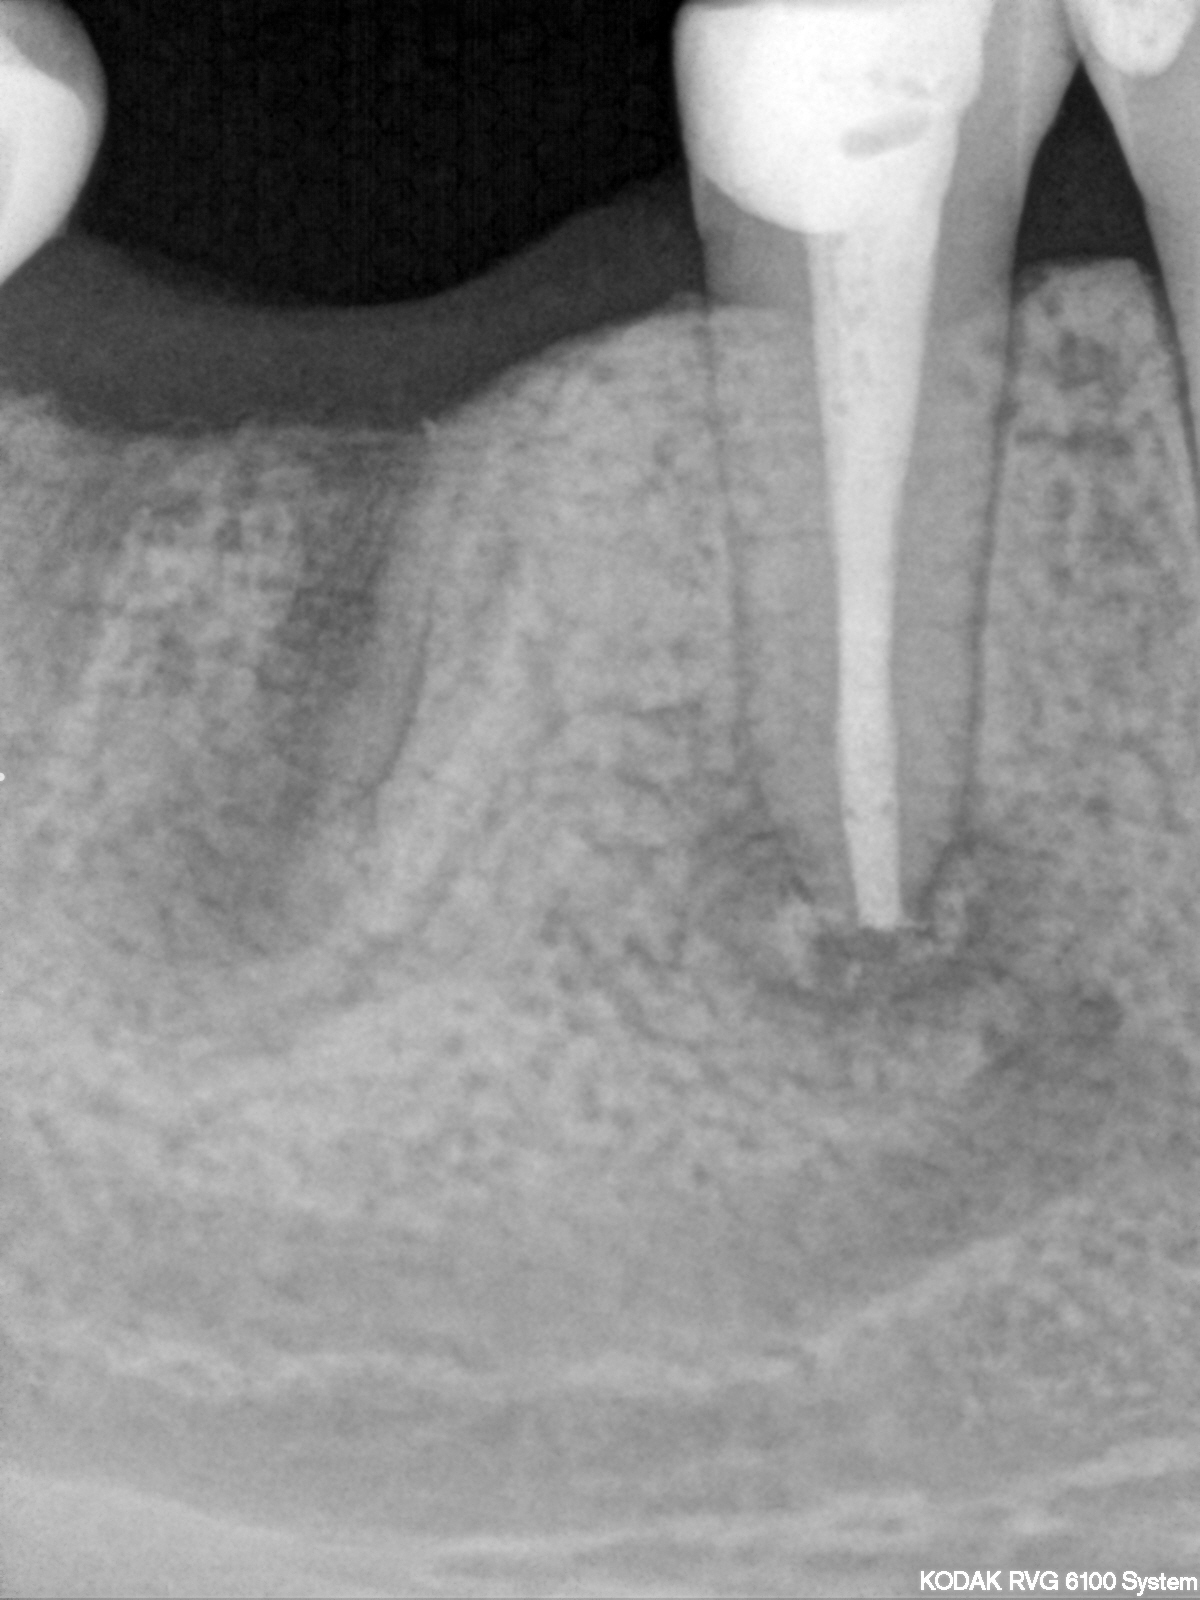

Saving hopeless teeth (35)